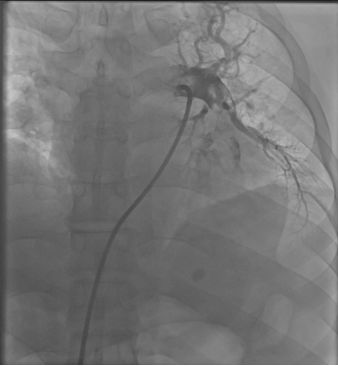

修正诊断:急性肺栓塞。给予阿替普酶50 mg静脉溶栓,之后依诺肝素80 mg ih q12h。复查血气分析:pH 7.5(↑),PCO225.2 mmHg(↓),PO264.9 mmHg(↓),SO294.5%(↓),PO2(A-a)50.0 mmHg(↑)。患者仍觉活动后胸闷,于2014年11月5日行肺动脉造影、肺动脉血栓导管碎解及血栓抽吸,术中测肺动脉压为60/27 mmHg,手推造影剂,可见肺动脉近段多处充盈缺损,先后送入7F长鞘,反复捣碎、抽吸,抽出大量新鲜血栓。再次造影后见肺动脉充盈缺损明显减轻(图2)(图3),测肺动脉压为47/8 mmHg。其后给予阿替普酶50 mg+生理盐水50 ml,2小时静脉泵入。泵入完毕后给予依诺肝素80 mg ih q12h,加用华法林抗凝。术后1周复查肺动脉CTPA示左、右肺动脉主干血栓消失,远端分支少许血栓(图4)。病情好转出院。

图2.左肺动脉造影见明显充盈缺损